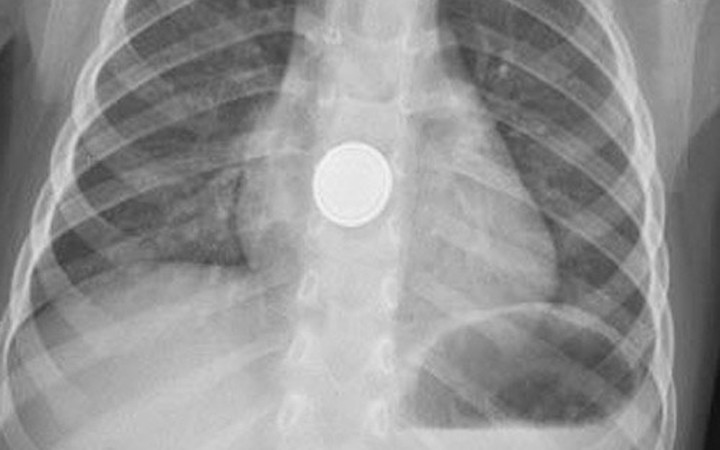

Küçük Efe pil yutunca olanlar oldu - Resim: 1

Tarsuslu İbrahim ve Sibel Işık çiftinin tek çocukları Mehmet Efe Işık, evde oyun oynarken, baskülün 3.5 santimetre çapında ve 2 milimetre kalınlığındaki yuvarlak pilini yerinden çıkarıp yuttu. Küçük çocuk, ağzına aldığı pili yuttuktan kısa süre sonra yemek borusunda yanma hissetti. Annesinin yanına giden çocuk, 'Ben pil yuttum. Boğazım yanıyor' demesi üzerine ailesi tarafından hemen Medical Park Hastanesi Acil Servis'e götürüldü.

Acil Servis'te ilk müdahalesi yapılan ve filmi çekilen Mehmet Efe'yi ardından Gastroenteroloji Uzmanı Dr. Hüseyin Sancar Bozkurt'a yönlendirdi.